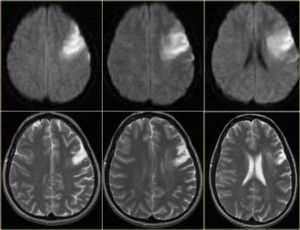

Выделяют острую и хроническую ишемию головного мозга. Острая ишемия возникает при резком развитии кислородного голодания и протекает по типу транзиторной ишемической атаки или ишемического инсульта (инфаркта мозга). Хроническая ишемия формируется постепенно в ответ на длительно существующую недостаточность мозгового кровообращения.

В 1-й стадии доминируют субъективные расстройства в виде головных болей и ощущения тяжести в голове, общей слабости, повышенной утомляемости, эмоциональной лабильности, головокружения, снижения памяти и внимания, нарушения сна. Эти явления сопровождаются хотя и легкими, но достаточно стойкими объективными расстройствами в виде анизорефлексии (разность симметричных сухожильных рефлексов), дискоординаторных явлений, глазодвигательной недостаточности, симптомов орального автоматизма, снижения памяти и астении. В этой стадии, как правило, еще не происходит формирования отчетливых неврологических синдромов (кроме астенического) и при адекватной терапии возможно уменьшение выраженности или устранение как отдельных симптомов, так и заболевания в целом.

В жалобах больных со 2-й стадией ХИМ чаще отмечаются нарушения памяти, потеря трудоспособности, головокружение, неустойчивость при ходьбе, реже присутствуют проявления астенического симптомокомплекса. При этом более отчетливой становится очаговая симптоматика: оживление рефлексов орального автоматизма, центральной недостаточности лицевого и подъязычного нервов, координаторные и глазодвигательные расстройства, пирамидная недостаточность, амиостатический синдром, усиление мнестико-интеллектуальных нарушений. В этой стадии возможно вычленить определенные доминирующие неврологические синдромы — дискоординаторный, пирамидный, амиостатический, дисмнестический и др., которые могут помочь при назначении симптоматического лечения. На этом этапе уже нарушается социальная и трудовая активность больного, в некоторых случаях даже в повседневных делах уже требуется помощь посторонних людей. Полностью обратить изменения, произошедшие в нервной системе невозможно, но можно нивелировать симптоматику и замедлить прогрессирование заболевания.